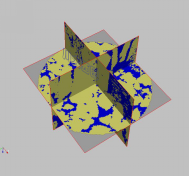

4、三维图像重建及分析

三维重建是指对三维物体建立适合计算机表示和处理的数学模型,是在计算机环境下对其进行处理、操作和分析其性质的基础,也是在计算机中建立表达客观世界的虚拟现实的关键技术。

8、石油地质图像处理应用系统开发